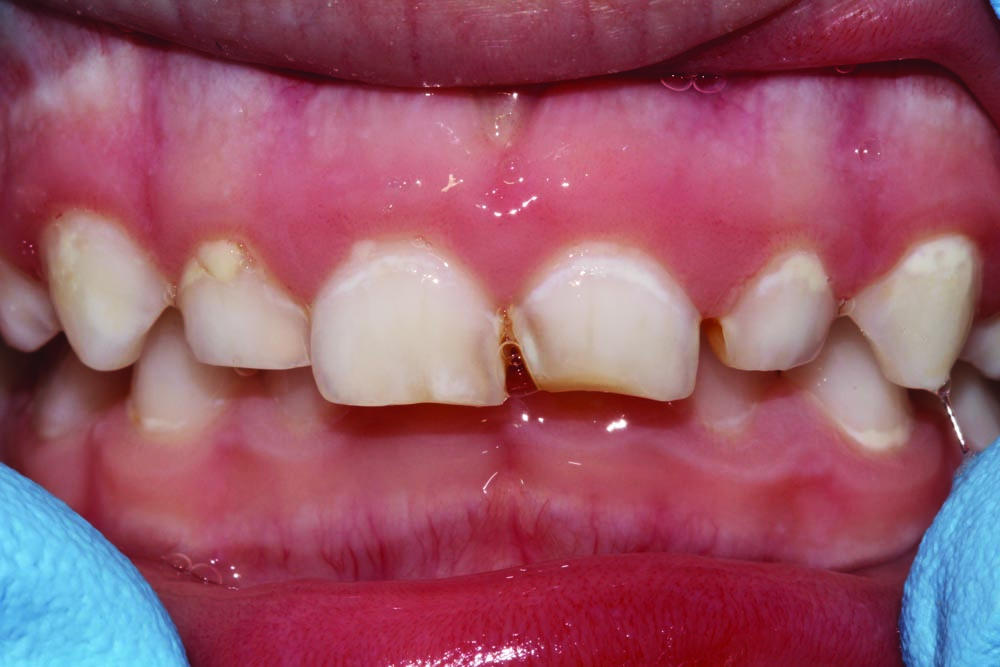

A shy and apprehensive 3-year-old female patient presented with multiple caries in all quadrants. To keep the patient's in-office experience positive, all posterior teeth were restored with a combination of atraumatic restorative techniques and minimally invasive techniques.

Maxillary anterior incisors #52–#62 (D–G) all exhibited varying depths of decay and required restoration (Fig. 6). Only topical anesthetic was used, and the area was isolated with cotton rolls. Teeth were minimally prepared into enamel only with an NSK high-speed handpiece and a tapered rough grit diamond FG bur.

Caries was excavated with a spoon excavator (Fig. 7). Because isolation was a challenge, all surfaces of affected teeth were bonded with a self-etch procedure using Futurabond U and then light-cured (Fig. 8). Celluloid strip crowns were fitted and vented, filled with GrandioSO by Voco, seated and light-cured.